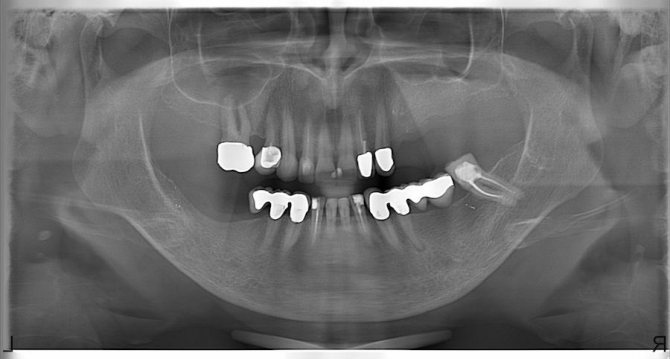

Если визуальный осмотр не дает в полной мере оценить сложность случая, пациенту рекомендуется пройти одно из обследований — рентгенография, КТ (компьютерная томография), ортопантомография или визиография.

Если предстоит сложное удаление, выполняется весь комплекс этих обследований. По полученным результатам стоматолог может четко установить количество и строение корневой системы, выяснить направление их роста и степень кривизны, рассчитать объем и продолжительность предстоящей манипуляции, подготовить соответствующие инструменты.

Если стоматолог удалял сложный зуб и у него имеются некоторые сомнения относительно чистоты лунки, он обязательно направит пациента на повторное рентгеновское обследование по завершению операции.

Это делается с целью предотвращения развития послеоперационных последствий, связанных с оставлением кусочка корня в альвеоле.